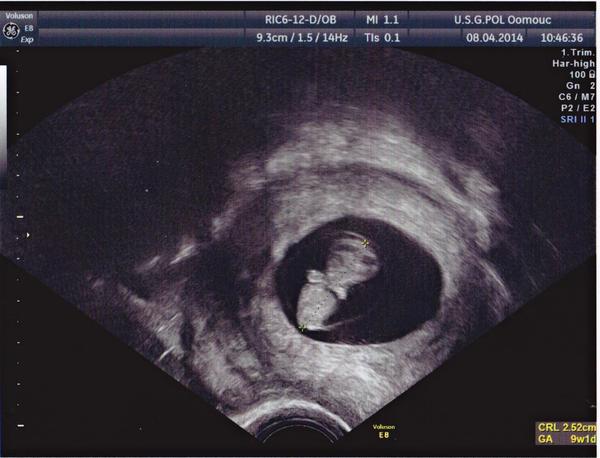

kifsepixam (28 let, MA ve 21tt,10/2013, kys.list.,Femibion, injekce B12, Flexiparin)........70DC // 27.2. KO 22.4.